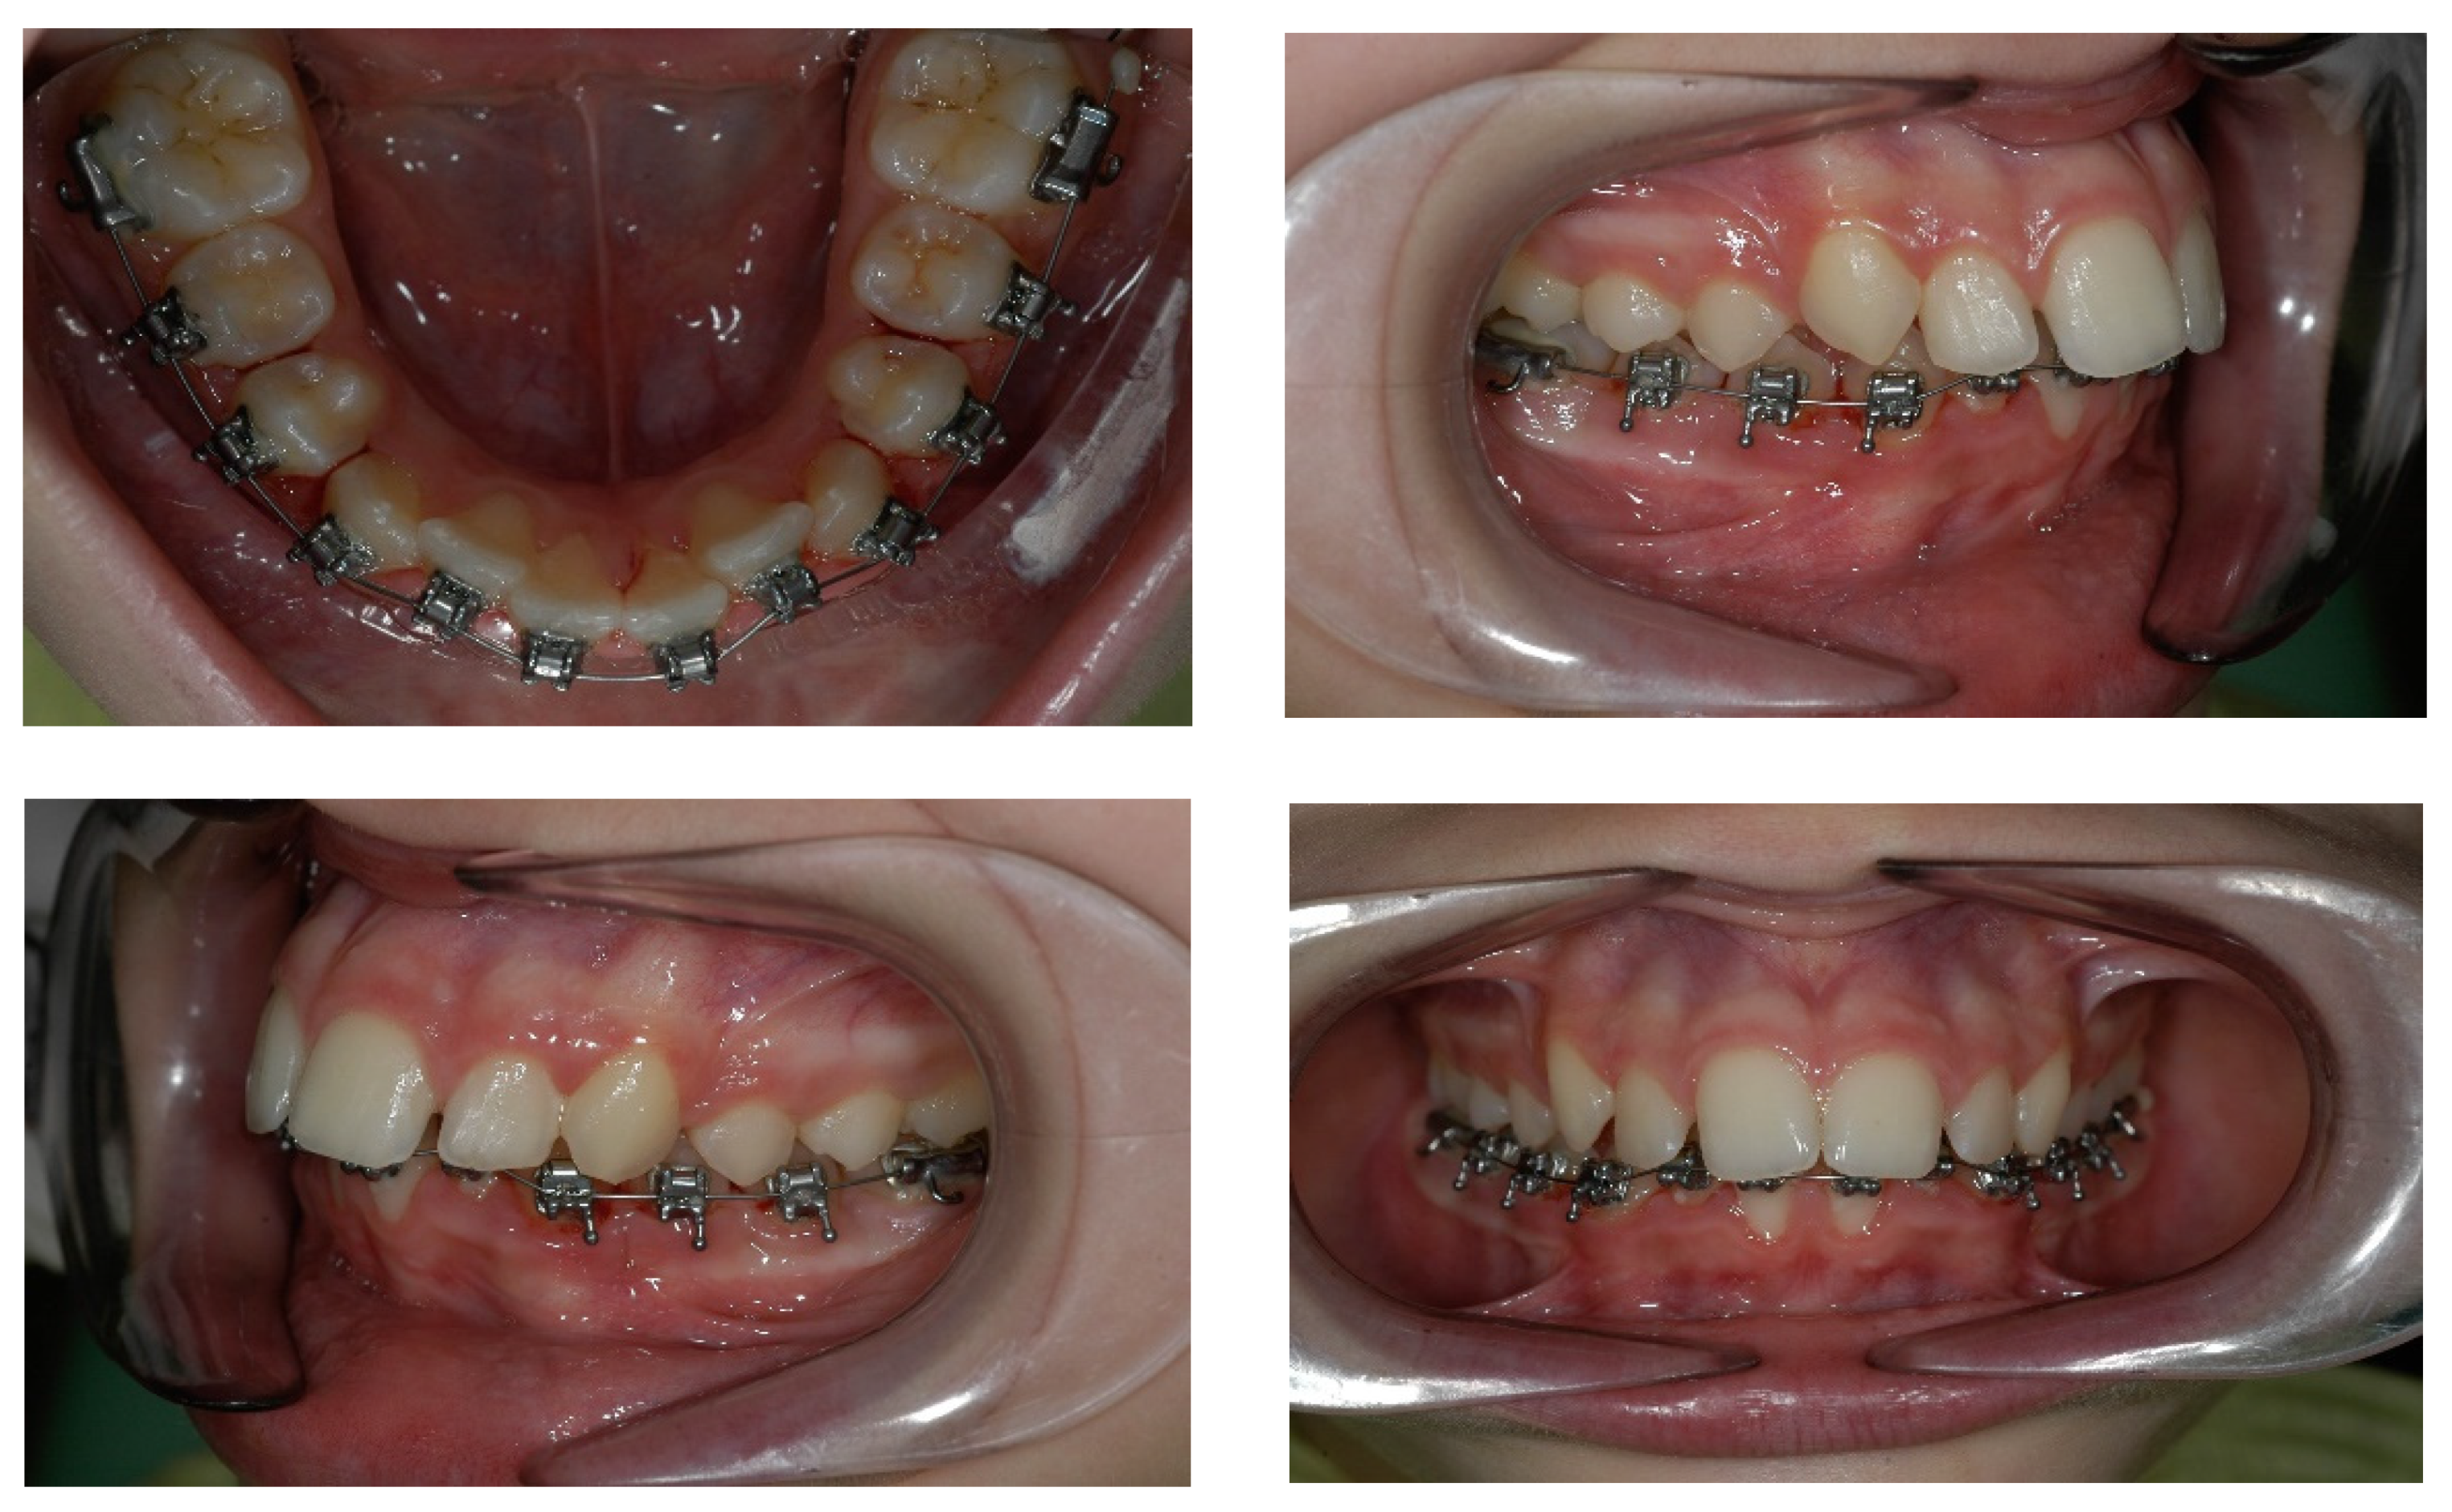

4. Case Report

4.1. Etiology and Diagnosis

4.2. Treatment Objectives

4.3. Treatment Strategy

4.4. Treatment Progress